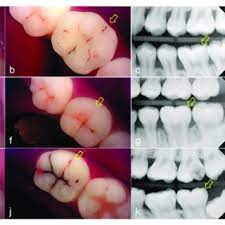

Dental Caries Etiology Clinical Characteristics Risk Assessment And Management Dentistrykey

vizitati articolul complet aici : https://dentistrykey.com/library/dental-caries-etiology-clinical-characteristics-risk-assessment-and-management/